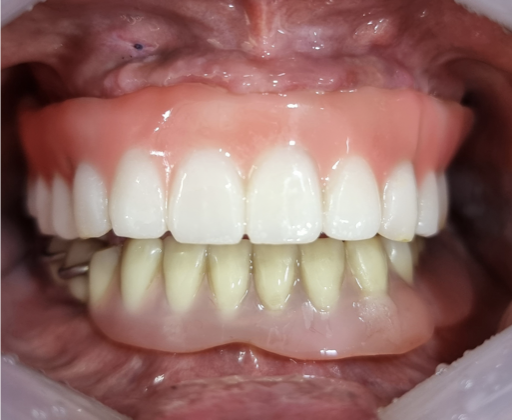

바른이치 치과의 더 이상 실패하지 않는 임플란트 재수술

임플란트를 식립하는 치과는 많이만 재수술하여 성공하는 치과는 극소수입니다.

바른이치 치과의 임플란트 재수술은 풍부한 임플란트 재수술 임상경험의 15년 이상 경력의 구강악안면외과 전문의 대표원장이 임플란트가 실패할 수 있는 모든 경우에 대응합니다.

바른이치 치과는 성공적이고 만족스러운 임플란트 재수술을 약속드리겠습니다.